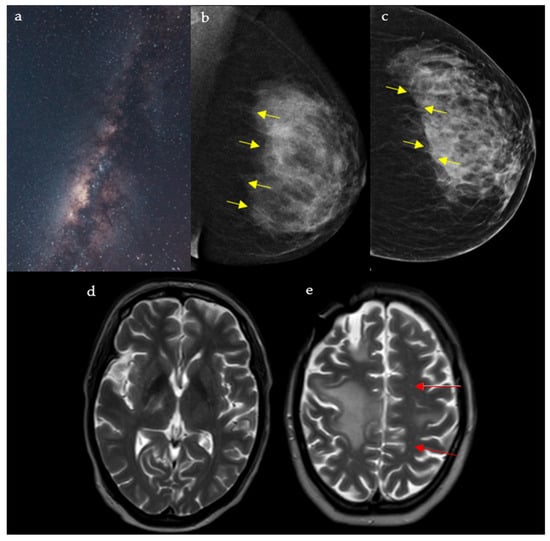

Cosmic Signs in Radiology: A Pictorial Review

Pattern recognition remains a cornerstone of radiologic interpretation, as it facilitates a confident and comprehensive differential diagnosis. Certain pathologies present with specific and highly recognizable patterns on imaging modalities. These patterns can resemble familiar real-life phenomena, including cosmic bodies that surround us. We present in this article a compilation of radiologic signs across various modalities that take inspiration from cosmic phenomena. For each sign, we summarize its defining imaging appearance, typical clinical context, and common pitfalls; where available, we note diagnostic performance (e.g., sensitivity/specificity) to guide appropriate weighting in practice. By coupling memorable imagery with succinct clinical guidance, this pictorial review aims to support a faster, more accurate pattern recognition that is applicable in both low-resource and tertiary care settings, while recognizing that these signs function as educational aids rather than validated diagnostic tests. In familiarizing themselves with these classic signs, training radiologists can benefit from an engaging and memorable way of recognizing various pathological conditions. Full article

Figure 1